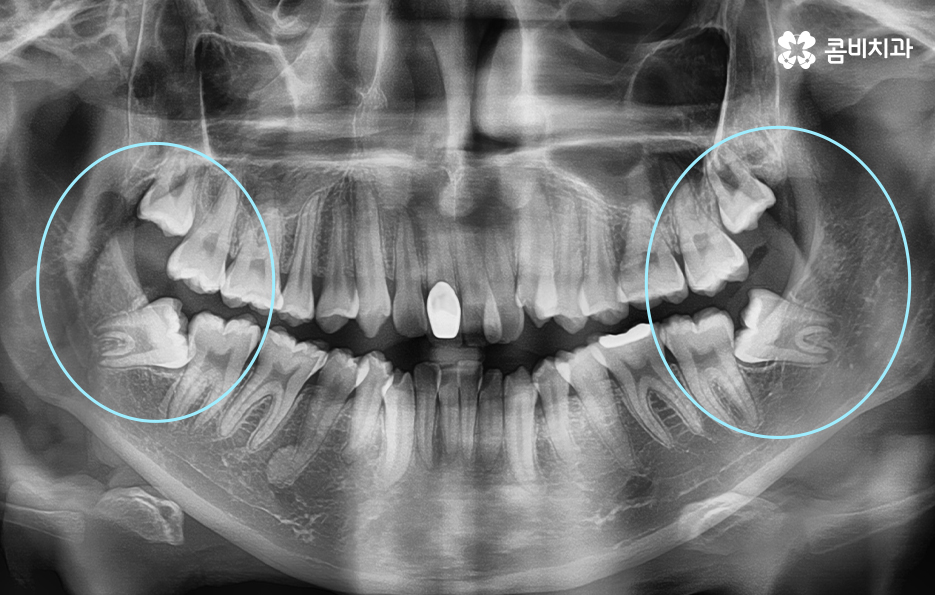

위 사례와 같이 턱이 좁은 경우에 사랑니 역시 제대로 맹출 될

공간이 부족한 경우가 많으며 사랑니가 누워서 자라는 경우에

어금니를 밀어내면서 치열을 더욱 망가지게 할 우려가 있으니

성인 이후에 치열이 불규칙해진 경우라면 사랑니의 체크가 꼭 필요할 수 있어요.

위 환자분의 케이스는 아랫니에 치아 2개를 발치하여

치아의 이동 공간을 확보하였고 발치교정이 진행될 때는

윗니와 아랫니 각각 2개씩 발치를 하는 경우가 많지만

위 사례는 치열, 교합 등을 고려할 때 아랫니 2개만

발치가 진행되었던 경우라고 볼 수 있어요.